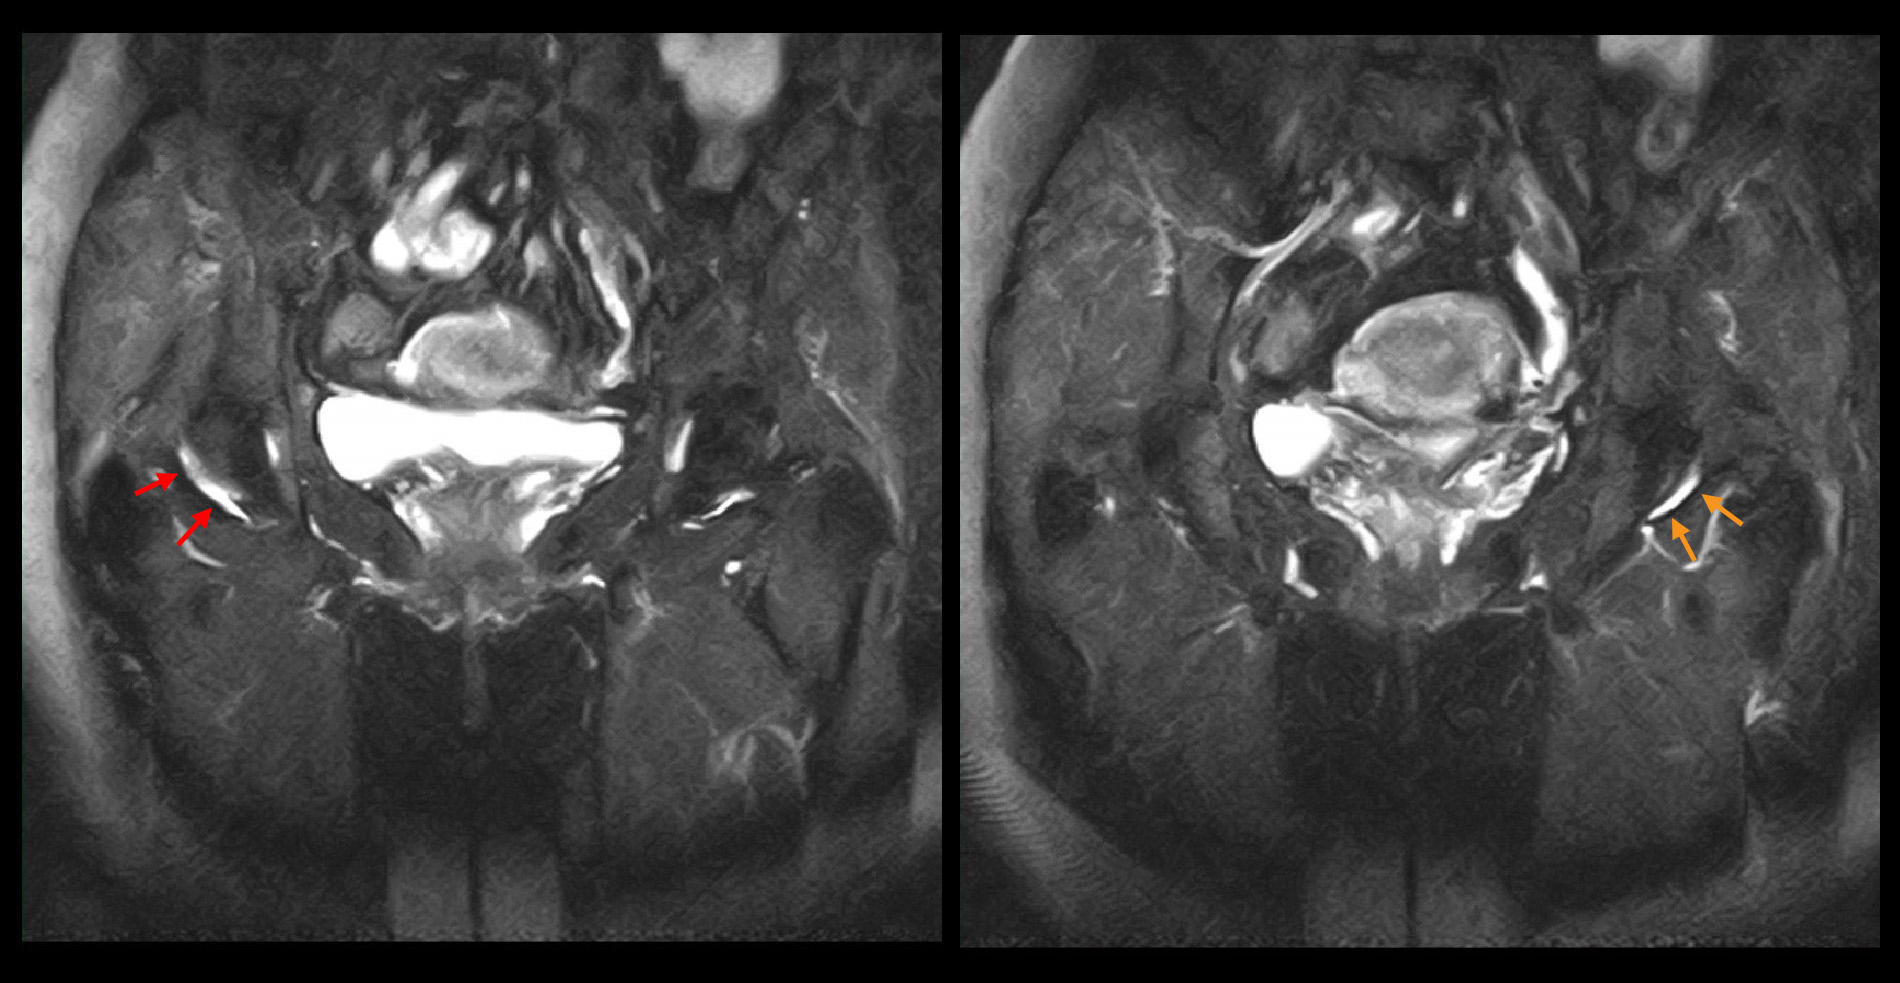

パトリック兆候という股関節の異常を示す理学所見が確認されましたが、股関節のレントゲン像も異常を認めません。

股関節MRI検査では赤矢印は軽微な右股関節炎を示しますが、オレンジ矢印でも左股関節の軽微な股関節炎の所見が確認され、左右差はないと判断されます。